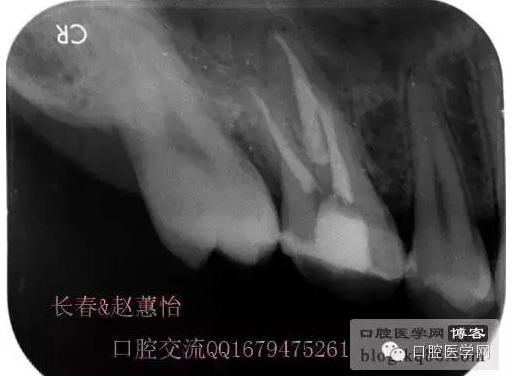

看多了文字眼花繚亂了吧,今天一個(gè)根管內(nèi)有臺(tái)階的患牙被充填上了,刻意投照了N多的X光片終于有一個(gè)給力的了,仔細(xì)觀察,可以看得見喔,也算是辛苦努力給個(gè)安慰獎(jiǎng),很多都是從片子上看不出有什么不同的。

這個(gè)是術(shù)前照片,一切如常

患牙是死髓牙,患者是一位大學(xué)生,探查根管時(shí)一切都很順利,就有點(diǎn)忽視了,當(dāng)然這個(gè)臺(tái)階是人為造成的,造成的原因呢就是使用機(jī)擴(kuò)時(shí)跳號(hào)了,所以大家一定要逐號(hào)使用啊,預(yù)備出一個(gè)臺(tái)階,后續(xù)要搭上很長(zhǎng)時(shí)間才能搞定,好不容易越過臺(tái)階下去的銼,一提拉出來就下不去了,著實(shí)讓人郁悶,一切都要從頭再來,這個(gè)時(shí)候再下銼的時(shí)候就必須預(yù)彎了。而且要多角度試探,很是考驗(yàn)?zāi)托牡臅r(shí)候。吃一塹長(zhǎng)一智嘛!

術(shù)后,明顯可見近中頰側(cè)根管臺(tái)階位置

越過臺(tái)階后小心預(yù)備直至大錐度銼可以順利進(jìn)術(shù)前片的小彎沒當(dāng)回事,哎